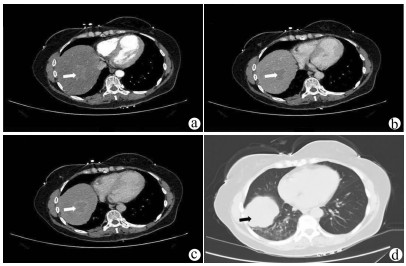

Surgical resection of liver metastases of ovarian cancer and the affected diaphragm and lung lobes via the intercostal approach: A case report

Daqun LIU, Ziyue WANG, Yushi CAO, Xing LYU, Guoyue LYU

2021, 37(11): 2649-2650. DOI: 10.3969/j.issn.1001-5256.2021.11.033

Abstract(773) HTML (441) PDF (2420KB)(53)

Abstract: